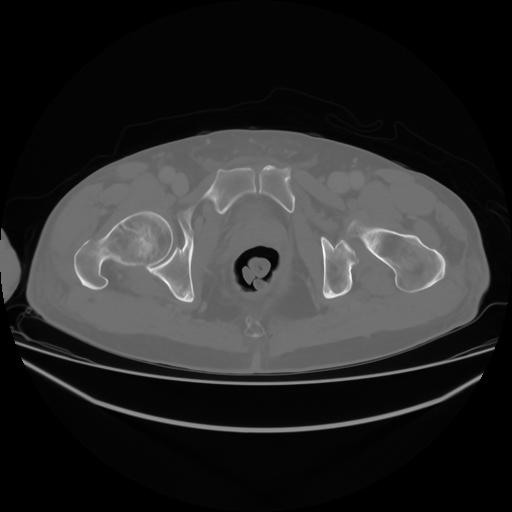

4 CUERPO,CE,Axial,3.0,CUERPO,,